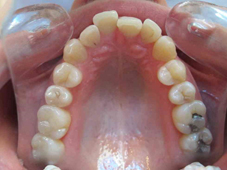

Arcade maxillaire avant traitement orthodontique, séquelles de maladie parodontale

Après traitement orthodontique et réalisation d’une attelle coulée collée (courtoisie Dr Patrick Fournier)